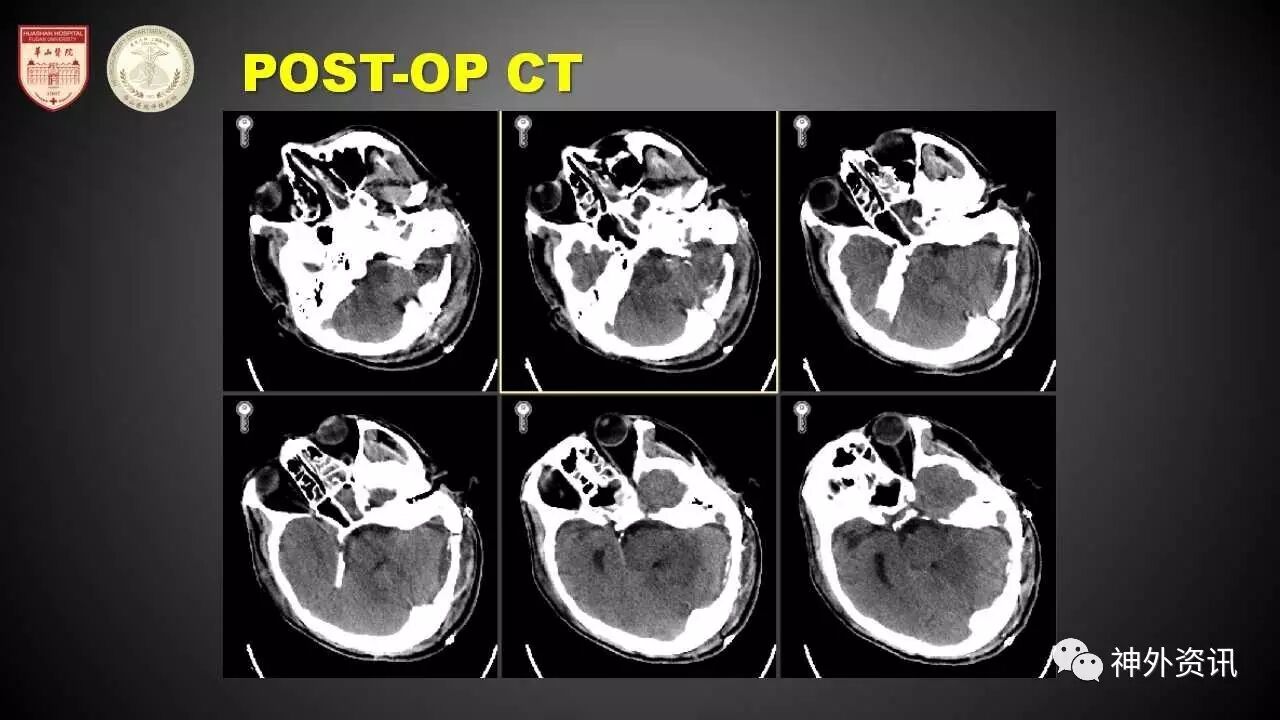

该患者是一例中老年患者,因突发头痛及意识丧失一天入院。入院后体检时患者已呈清醒状态,GCS 15分,无明显的神经功能损害的体征。发病时的头部CT提示明显的SAH(改良Fisher III级)。在出血急性期内所做的第一次DSA提示左侧小脑后下动脉近端动脉瘤。但该动脉瘤从形态上来看,无论是介入或手术处理均极为困难。该患者保守治疗2周余后,于华山医院复合手术室开展进一步诊治。复查术中DSA造影提示动脉瘤的瘤体变化增大。经由毛颖教授、顾宇翔教授和陈亮教授联合会诊后,考虑通过手术夹闭进行治疗。手术由陈亮教授主刀。患者改予左侧枕下远外侧入路开颅。打开硬膜后,通过逆行分离,松解远端蛛网膜,找到动脉瘤远端和椎动脉远端,然后锐性分离瘤顶,最后再探查载瘤动脉的近端。术中采用一枚弯夹将动脉瘤菲薄出血的瘤体夹闭。由于该动脉瘤内有硬化夹层可能,因此虽然成功将瘤体夹闭后,载瘤动脉仍呈梭状。进一步探查近端血管,确认夹闭满意,多普勒超声检查也提示载瘤血管通畅。值得注意的是,由于载瘤动脉内的硬化,尝试再予一枚动脉瘤夹塑形时,虽然载瘤血管的形态更好,但通过多普勒超声检查,可发现远端的血流实际上已闭塞。因此去除了第二枚动脉瘤夹。夹闭后即时复查的术中DSA提示夹闭效果满意,载瘤动脉的血流通畅。